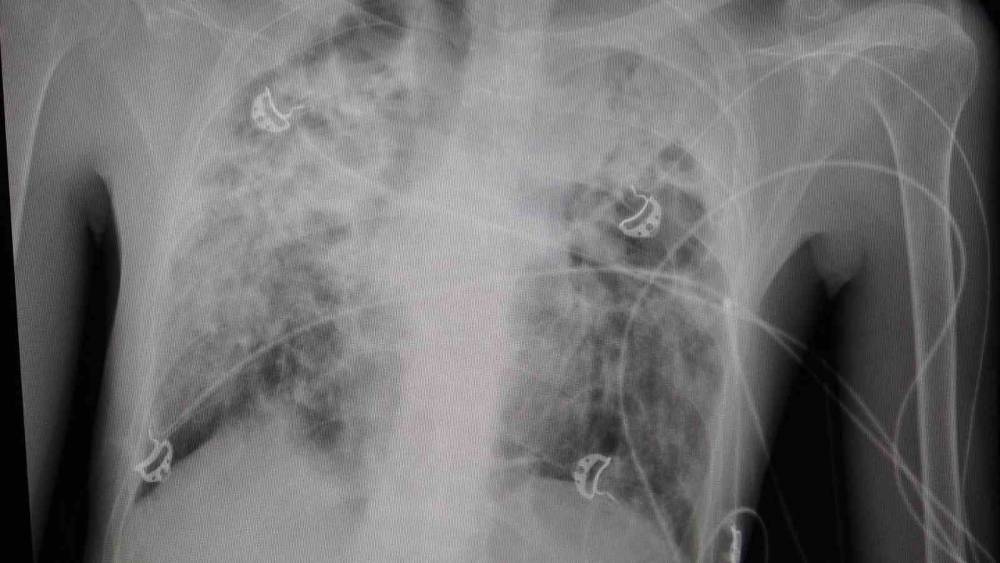

"Hastamızın yaşaması için tek çare nakildi"

Göğüs Cerrahisi Uzmanı Prof. Dr. Ahmet Erdal Taşçı, akciğer nakli bekleyen hastanın yıllardır bronşektazi hastalığıyla mücadele ettiğini belirterek, "Hastamızın yaşaması için tek çare nakildi. Nakil başarılı geçti. Bu operasyon, bizim ekibimiz için teknik anlamda standart bir akciğer nakliydi. Ancak dikkat çeken nokta, aynı anda hastanemizde bir karaciğer nakli operasyonunun da gerçekleştirilmiş olmasıydı. Aynı bağışçının organları, iki ayrı hastaya; biri akciğer, diğeri karaciğer olarak nakledildi. Bu vesileyle bağışçımıza Allah’tan rahmet, yakınlarına da sabır diliyoruz. Böylesine acılı bir anda başkasının hayatına dokunabilmek, örnek bir davranış" dedi.

"Yeni akciğerleriyle nefes alacak"

"Organ nakli, bir ülkenin sağlık sisteminin ne kadar gelişmiş olduğunu gösteren önemli bir göstergedir." diyen Taşçı, "Ameliyatı gerçekleştirilen hastamız, yoğun bakımda uyanık ve solunum desteğiyle izleniyor. Kısa sürede yeni akciğerleriyle nefes alması bekleniyor" diye konuştu. Taşçı, "Türkiye’de özellikle kadavra donör organ bağışlarının artması büyük önem taşıyor. Herkesin bir gün kendisinin veya sevdiklerinin de bu ihtiyaca düşebileceğini düşünerek, organ bağışı konusunda daha duyarlı ve bilinçli hareket etmesi gerekiyor. Ülkemizde Sağlık Bakanlığı’nın bu alandaki organizasyonu ve altyapısı gerçekten çok iyi seviyede. Bu anlamda emeği geçen herkese teşekkür ediyoruz" ifadelerini kullandı.